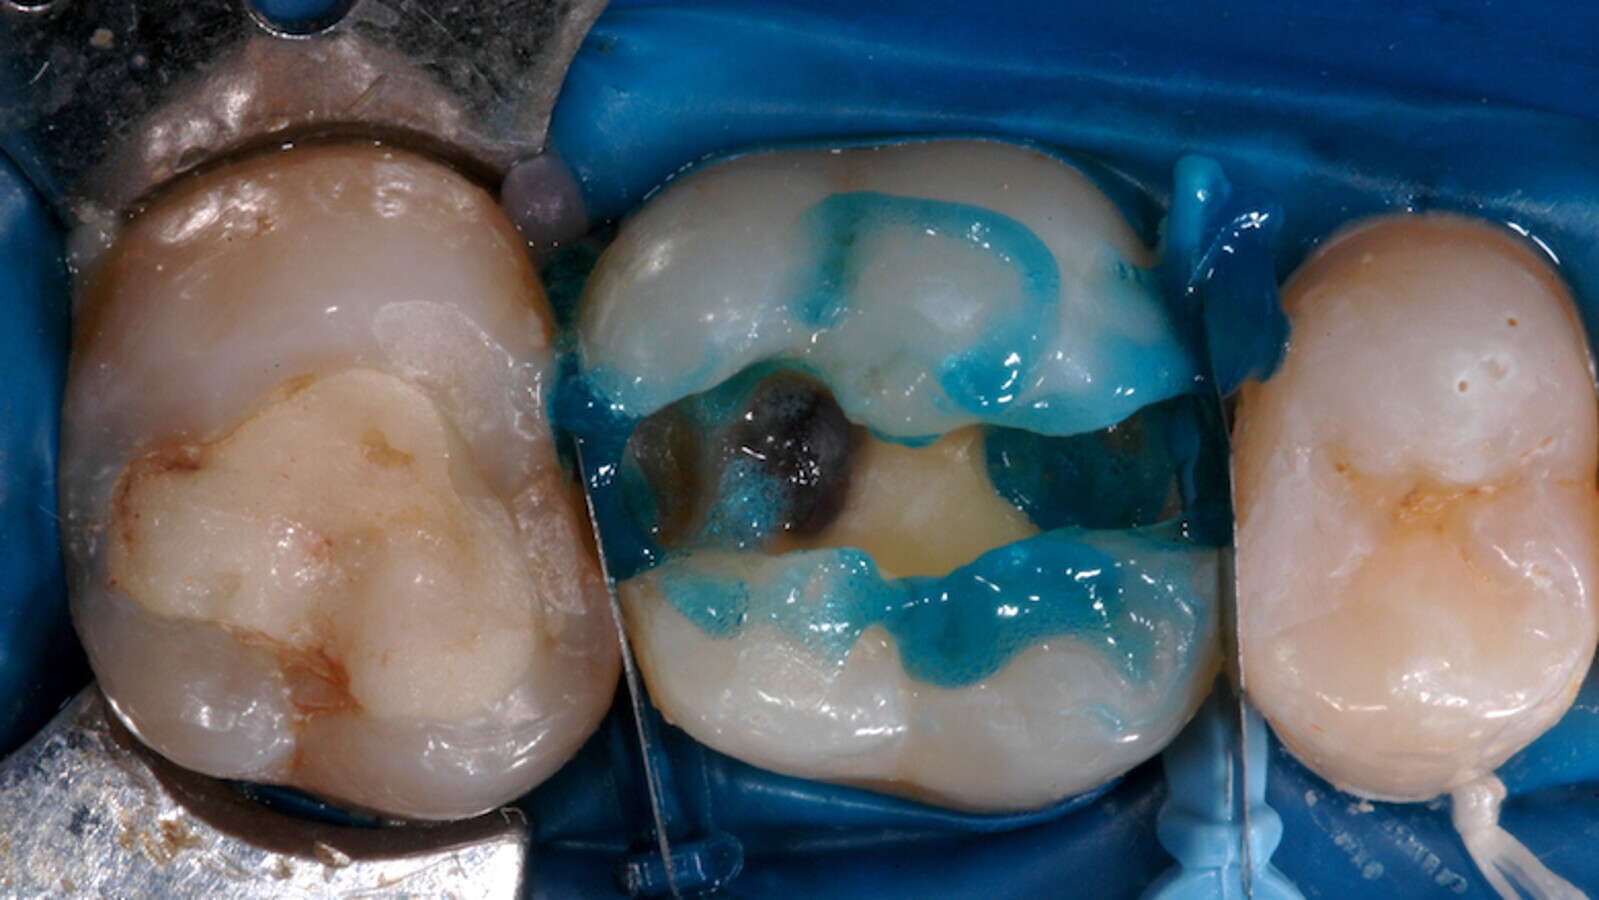

Foto 6. Luego de la preparación cavitaria se observa el grabado ácido total y la protección de las piezecinas.

Foto 7. Aplicación del SDR flow en una de las cajas proximales. Se observan las matrices proximales V3.